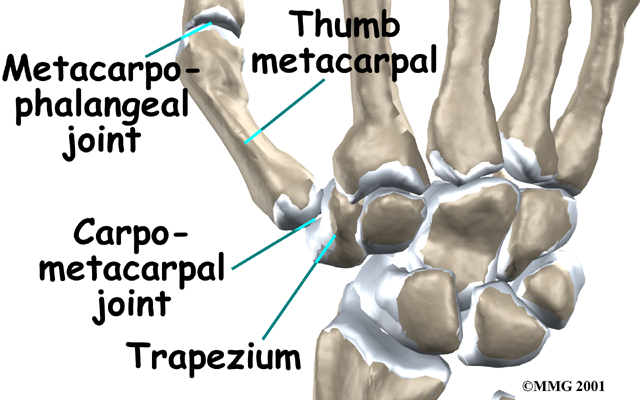

The carpometacarpal joint of the thumb (CMC joint) is where the metacarpal bone of the thumb attaches to the trapezium bone of the wrist. This joint is sometimes referred to as the basal joint of the thumb as it is the joint closest to the bottom of the hand. The CMC is the joint that allows you to move your thumb into your palm, a motion called opposition.

Several ligaments (bands of strong tissue) hold the bones of the joint together. These ligaments join to form the joint capsule of the CMC joint. The joint capsule is a watertight sac around the joint.

The joint surfaces are covered with a material called articular cartilage. This material is the slick, spongy covering that allows one side of a joint to slide against the other joint surface easily. When this material wears out, the joint develops a type of arthritis called osteoarthritis and becomes painful. Osteoarthritis is the most common form of arthritis occurring at this joint.